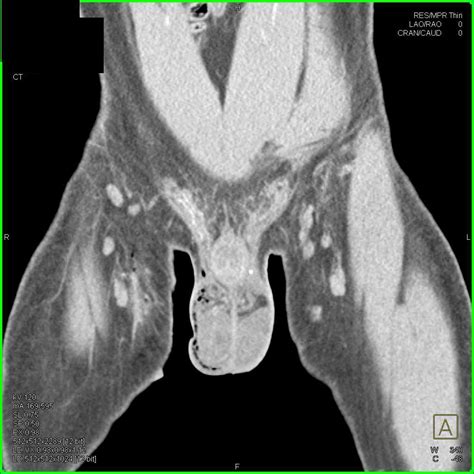

• Angiokeratomas: These are small, benign clusters of dilated blood vessels that can resemble blood blisters. They are common in older adults and are typically harmless.

• angiokeratoma pictures on balls